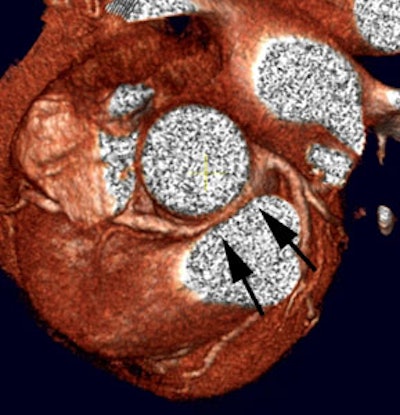

3D cardiac coronary angiography: 3 dimensional color image from a coronary CT angiogram. |

|